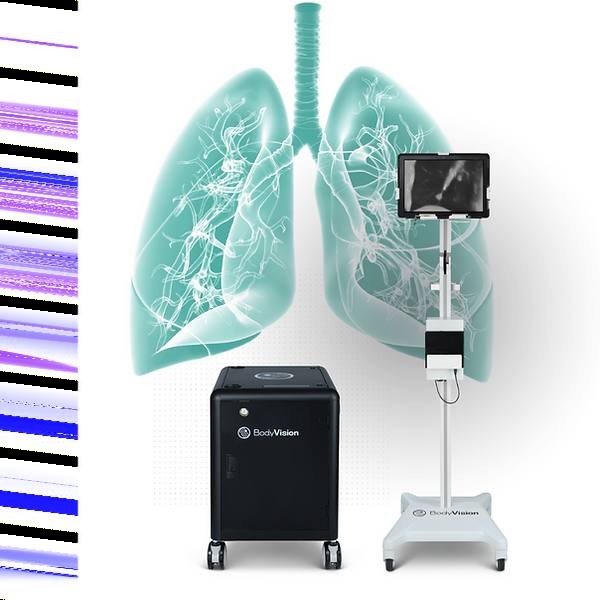

LungVision|Body Vision Medical

项目类型

器械质押区

起投金额

300000USDT

每日释放:1.2

释放周期:160 天

已购: 500

剩余: 0